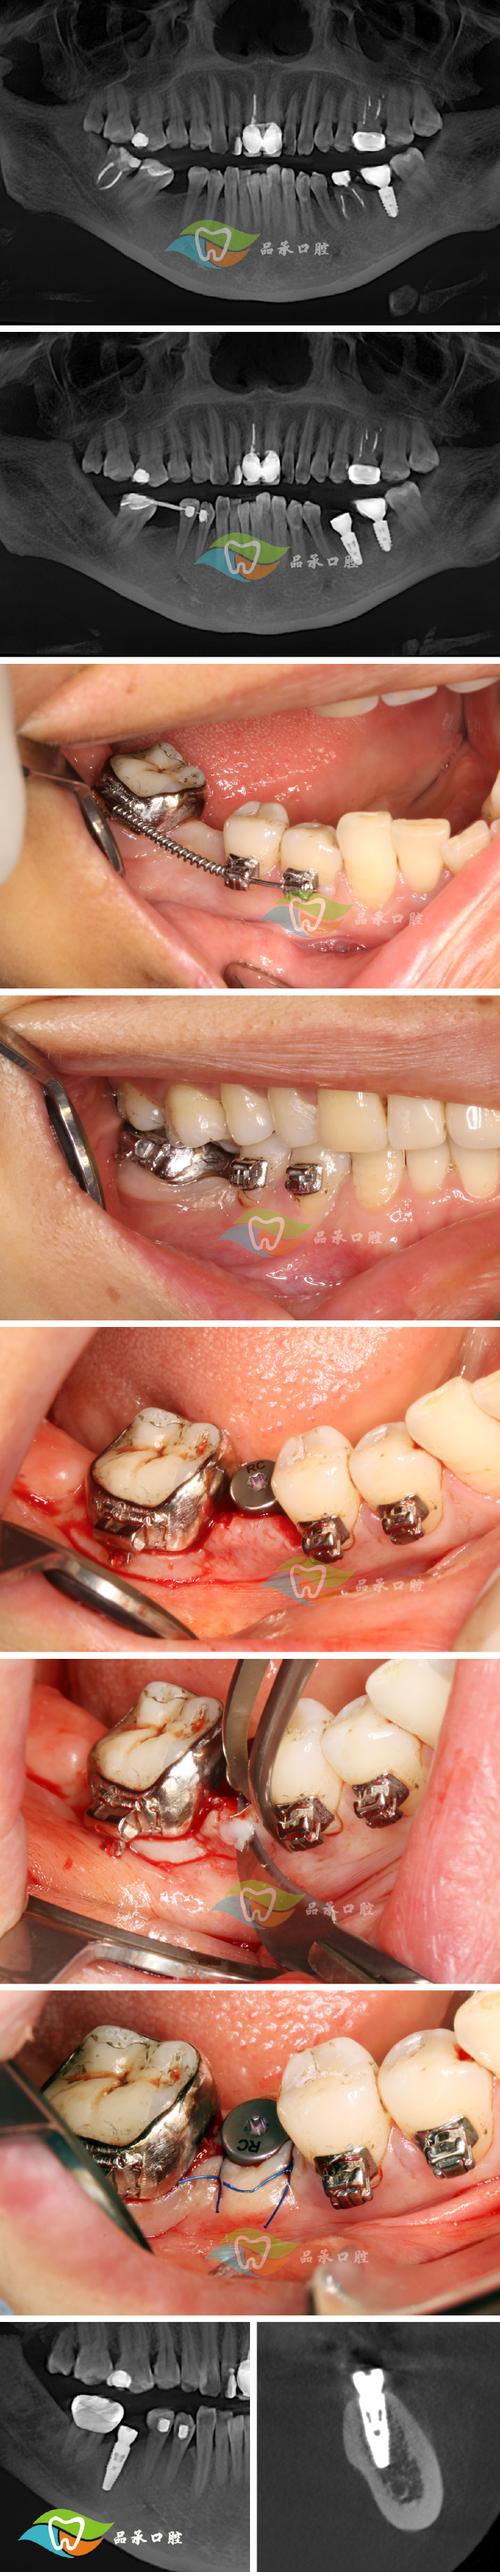

精准术前评估:用数据说话,避免“盲目种植”

急拔急种牙最关键的一步是判断牙槽骨条件,拜博口腔采用3D数字化CBCT+口扫仪,在拔牙前精准测量牙槽骨的厚度、高度、密度,以及神经血管的位置,确保种植体植入的位置、角度、深度都经过精密计算。

- 对于牙槽骨条件好(骨量充足、无严重吸收)的患者,可直接进行即刻种植;

- 对于牙槽骨轻微不足的患者,可通过“骨粉骨膜引导再生技术”同期或延期种植,避免二次手术;

即刻种植技术:“当天种牙”,缩短治疗周期

拔牙后,医生会在新鲜的牙槽窝内立即植入种植体(相当于“人工牙根”),拜博口腔采用亲水性种植体(如瑞典NobelActive、瑞士ITI),其表面特殊处理技术可促进骨细胞附着,骨结合速度比传统种植体快30%,缩短了“等待骨结合”的时间。

- 前牙区美学修复:对于前牙外伤或龋坏的患者,拔牙后即刻种植,同时安装临时牙冠,当天即可恢复美观和基本咀嚼功能,避免“缺牙尴尬”;

- 后牙区功能修复:对于后牙缺失的患者,若牙槽骨条件允许,即刻种植后可安装“临时修复体”,1-3个月后更换永久牙冠,避免传统种植牙“3个月无牙可用”的困扰。